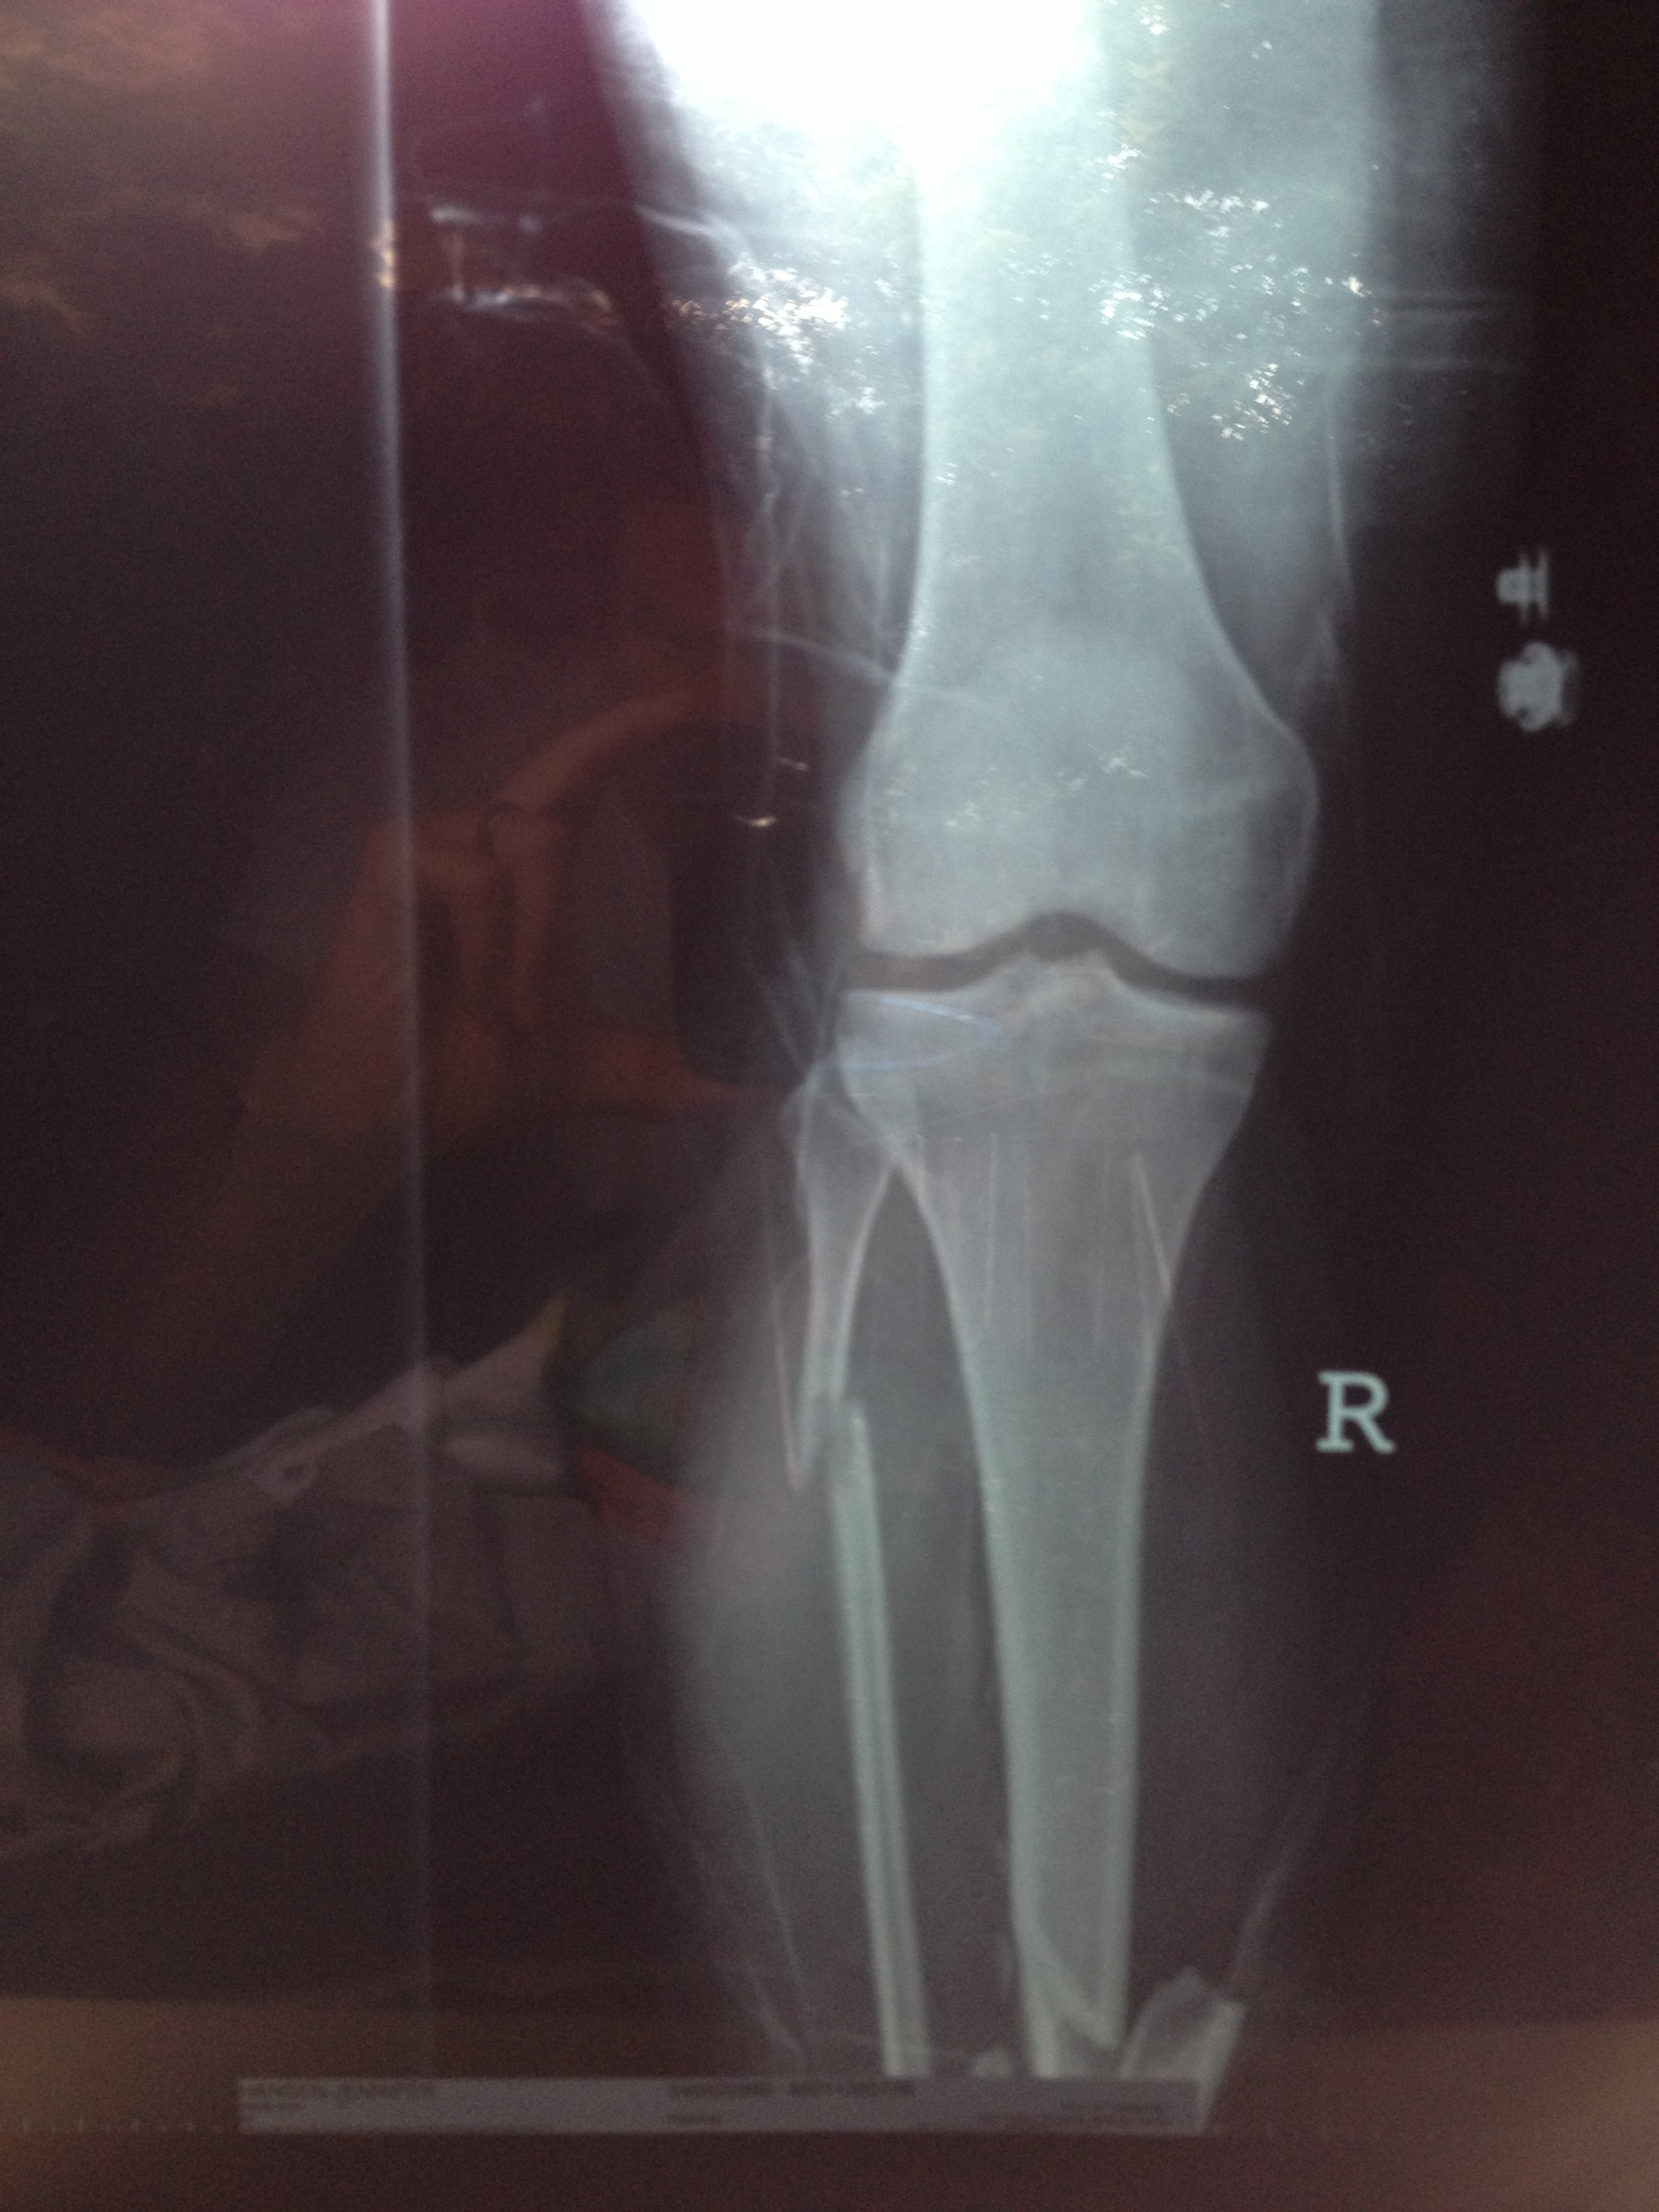

This is my running history, I started running in California when I was young and continued on in to high school. It is there where I learned and loved to compete. With my fastest time in the 1500 being 4:47 I was looked at by many universities. But unfortunatley at this time I was starting to feel burnt out from running and started seeing my times increase. So to avoid the pressure of any big university I chose to run for a junior college instead. After about a year of attending the junior college I decided to move to Utah to continue my education. I continued to run but not competitivley. I continued to feel sluggish as I did that senior year of high school. Then on Christmas day of 2001 driving home from work from the local ski resort I was in an accident. Heading down the canyon I drove over black ice that spun my Honda Civic out of control into the middle mediam. The impact force then caused my car to slide across the road on to the shoulder hitting the gaurd rail. Although, the momentum was great enough to rip the rail out if its anchors and it folded on its self. This caused a strengthing effect and the doubled up metal pushed through the front passenger side and out through the drivers door. The guard rail tore through the door of the Civic and out the otherside taking the seats with it. Miraculously leaving only one piece of precious cargo, ….me. Once the enertia ceased I was left sitting on top of the doubled up guard rail pinned against the steering wheel, legs caught between the clutch and the brake. It was truly a miracle I survived. The damage, although for me a runner was very serious, was very minimal and superficial. The trauma included the tearing of all ligaments in the left knee, two broken legs with one major compound fracture.

As one could imagine, this put my running on hold. I was hospitalized for two weeks followed by four months of being wheelchair bound not to mention the massive rod hammered into my right leg.